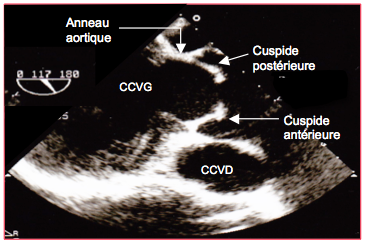

Figure 26.120 : Bicuspidie aortique en vue court axe. A : bicuspidie de type 0 avec une cuspide droite (1) et une cuspide gauche (2). B: bicuspidie de type 0 avec une cuspide postérieure (3) et une cuspide antérieure (4); la valve est grande et l'anneau dilaté (dilatation de la racine aortique dans un syndrome de Marfan). C : planimétrie d’une bicuspidie sténosée ; la surface d’ouverture est 0.5 cm2. D: bicuspidie en mode 3D.

En vue court-axe 40°, l'ouverture est en forme de fente, d'ellipse ou de banane selon la configuration (voir Figure 26.120). Dans le type 0, on ne compte que deux commissures, approximativement à 180° l'une de l'autre (Vidéo). Selon leur position, on parle de cuspide antérieure, postérieure, droite ou gauche. Comme le diamètre n’est pas égal à la moitié de la circonférence, le bord libre des deux cuspides ne peut pas rejoindre sa position normale en systole et reste tendu à mi-chemin entre la position fermée et la paroi des sinus de Valsalva. En long axe, ce phénomène donne un aspect typique en dôme (doming), avec une distance entre l’extrémité des feuillets < 1.5 cm (voir Figure 26.122). Dans le type I par contre, on aperçoit clairement trois commissures; la fusion de deux cuspides laisse une ouverture déformée entre la cuspide libre et les deux cuspides fusionnées (Vidéos). En systole, le bord libre des cuspides vibre dans le flux, ce qui génère un souffle systolique. Ce stress est à l’origine de la dégénérescence de la valve qui évolue vers la sténose ou l’insuffisance, en général à partir de 30-40 ans. En diastole, le corps d’un feuillet est typiquement plus ballonné que celui de l’autre.